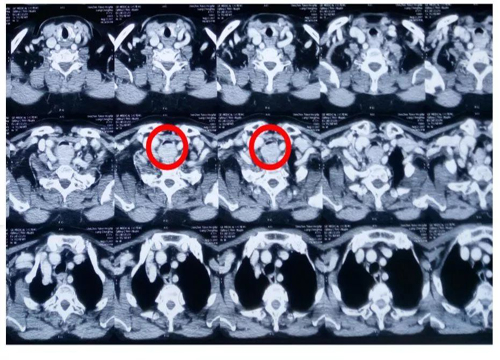

术前CT显示肿瘤将气管膜部顶入气管内,造成气管管腔狭窄,最小间隙3mm左右。术前气管镜检查不能进入到肿瘤下方,因患者呼吸困难无法耐受。患者自述平卧呼吸尚可。术前评估患者张口度、甲颏间距、头颈活动度均正常。

该患者肿瘤位于声门下2cm左右,正好相当于气管切开位置,如果先气切可能会切到肿瘤,外科气切不方便,希望先插管。患者于全麻诱导后插管,先用可视喉镜暴露声门,导管过声门后再用纤支镜引导通过肿瘤狭窄部位,选用5.0号管。手术过程顺利,术后待患者清醒,肌力恢复,呛咳后拔管返麻醉恢复室。